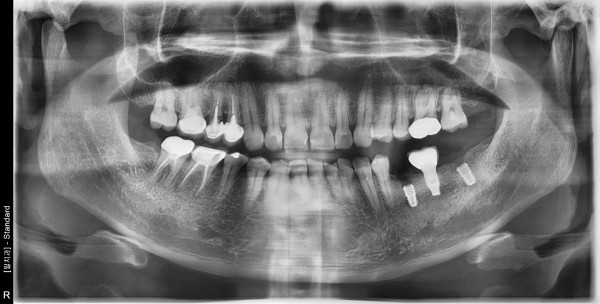

48세 남자환자 / 상악우측소구치 , 하악좌측 대구치및소구치 발치후 뼈이식 및 임플란트식립